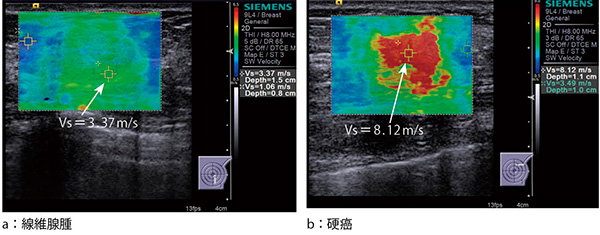

VTQが1か所だけの測定であったのに対して,VTIQはROIの中において,shear wave伝搬速度を瞬時に多点測定してカラーマッピングを行い,組織弾性イメージングを表示するものである。さらに,イメージングにカーソルを合わせることによって,局所部位の組織硬度(shear wave伝搬速度)を計数表示できる(図3)。

図3 VTIQによるshear wave elastography(乳腺)

(画像ご提供:亀田京橋クリニック画像センター・戸﨑光宏先生)